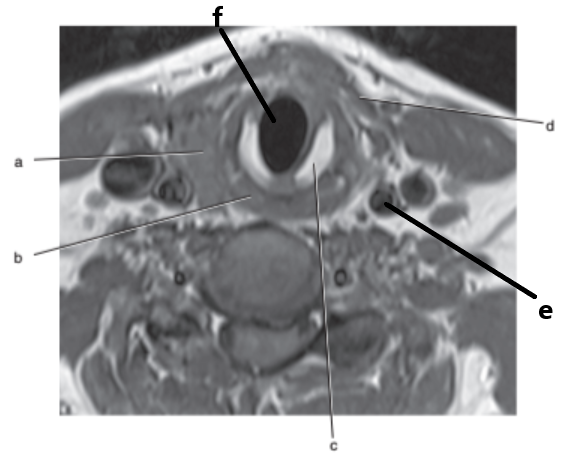

What imaging plane is this ?

transverse

What anatomy is letter b ?

Epiglottis

What is letter b ?

Thyroid gland

What is letter f ?

Spinal cord

Esophagus